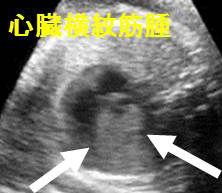

結節性硬化症(プリングル病)は全身に過誤腫とよばれる良性腫瘍ができます。心臓に横紋筋腫・リンパ脈管筋腫症(LAM)・腎血管筋脂肪腫・甲状腺結節(20.4%)、甲状腺乳頭癌(約1%)を認めます。